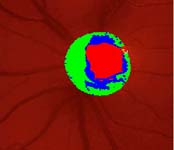

pacientka 1998

(tenze 40-50 torr) Na obrázcích vidíme terče levého oka pacientky, u které se ani opakovanými operacemi nepodařilo snížit nitrooční tlak.

pacientka 2001

Kromě zvětšení a vertikálního protažení exkavace je zřetelné zúžení arterií, zatímco vény jsou zúženy jen méně zřetelně.